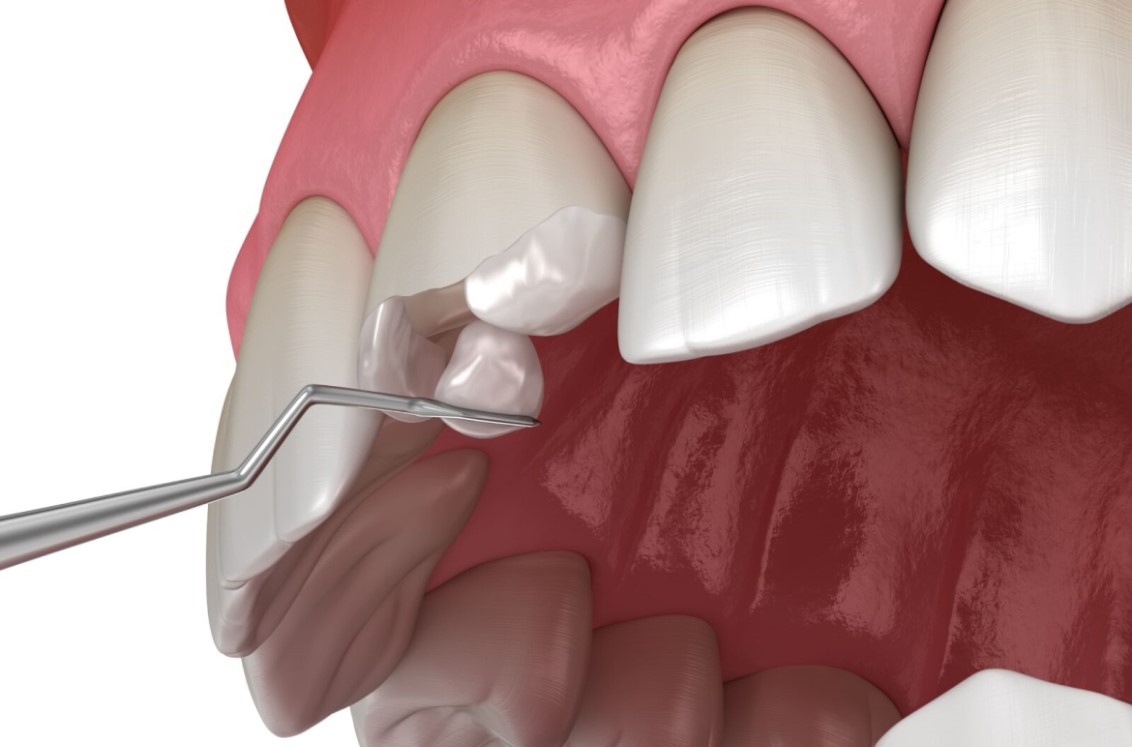

ابتدا دندانپزشک با استفاده از ابزارهای مخصوص، قسمت پوسیدهی دندان را پاکسازی میکند. سپس مادهی کامپوزیتی بهصورت لایهلایه روی دندان قرار گرفته و هر لایه با نور مخصوص (لایتکیور) سفت میشود. در نهایت، کامپوزیت فرم داده شده و پولیش میشود تا با بقیه دندانها هماهنگ گردد.